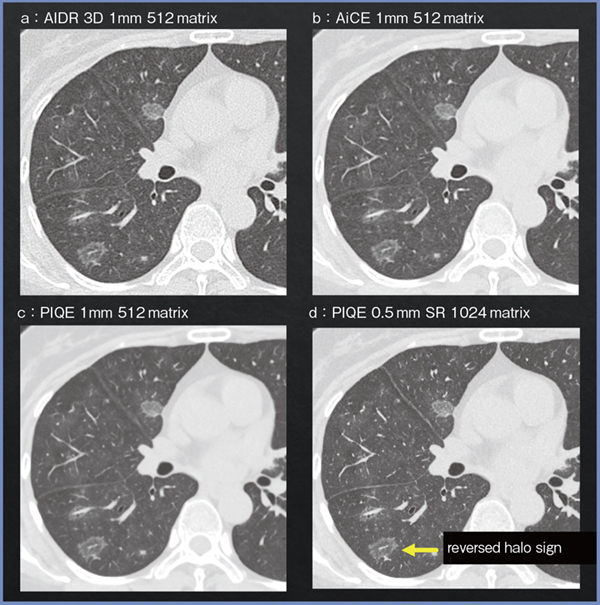

症例2は,50歳代,女性,甲状腺がん化学療法後の薬剤性肺障害疑いの症例である。AIDR 3D(図3 a)やAiCE(b)の画像と比較しPIQE(c,d)では,びまん性および斑状のすりガラス影が明瞭であり,斑状すりガラス影の辺縁には高吸収域(reversed halo sign:←)を認める。特に,0.5mm(SR)画像では,これらの所見がより明瞭である(図3 d)。MPRでも同様の所見を認めた。

図3 症例2:甲状腺がん化学療法後の薬剤性肺障害疑い